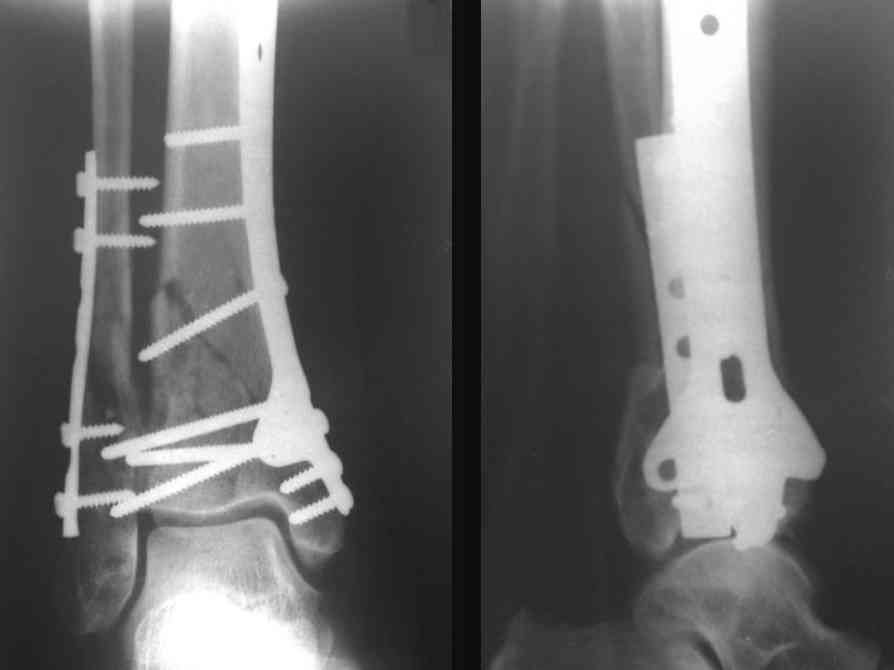

На рентгенограммах типичный перелом пилона по типу С-3. есть опыт до 100 открытых опреаций у нас в клинике. 20 примерно в год. Принцип один -все внутрисуставные переломы нуждаются в открытой репозиции и внутренней стабильной фиксации. При поступлении КТ не надо, так как получается только нагромождение костей. Истинной картины нет. Главное восстановить длину малоберцовой кости - это ключ к успеху. При поступлении меньше всего надо думать о сосудистых расстройствах, т.к. сама операция и репозиция даже сначала частичная даёт улучшение сосудитых нарушений. Причём очень быстро. Операция в 2этапа. При поступлении доступ позади наружной лодыжки, причём обязательно. После этого репозиция малоберцовой кости и фиксация пластиной 1/3 трубки под винт 3,5. Дренаж и любой аппарат наружной фиксации. Затем после спадения отёка на 5-7-10 день аппрат снимается и дугообразный разрез спереди от медиальной лодыжки 10-12 см. Главной чтобы расстояние между 1 и вторым разрезом было не меньше 7-8 см. Тогда не будет некрозов лоскутов. Таранная кость используется как матрица на неё укладываются отломки и фиксируются пицами. Ренг-контроль. Отломки лежат все отдельно, но ничего не высыпется. При переломах С-3 всегда нужна костная пластика (из крыла). Фиксация пластиной лист клевера простой или LCP. Гипс не нужен. Дренаж до 48 часов. Операция длится 3-4 часа обязательно без жгута. Посылаю примерно такой же случай.

Послала ещё два снимка, если не пройдут, пошлю ещё. Дрягин. Если есть вопросы, готов ответить.

Посылаю результат лечения предыдущего больного через год.